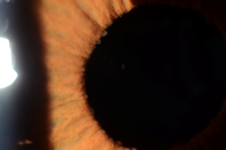

Precipitados difusos y estrellados, ausencia de sinequias.

Estos precipitados se localizan en forma difusa sobre todo el endotelio corneal sin formar el conocido triángulo de Arlt. Su tamaño es pequeño y la apariencia es estrellada. Estos pequeños depósitos tienden a confluir entre sí. La presencia de precipitados queráticos con estas características son suficientes para orientar el diagnóstico.

A pesar de ser un cuadro inflamatorio crónico, estos pacientes no desarrollan sinequias posteriores. Solamente pueden estar presentes luego de la cirugía de cataratas.